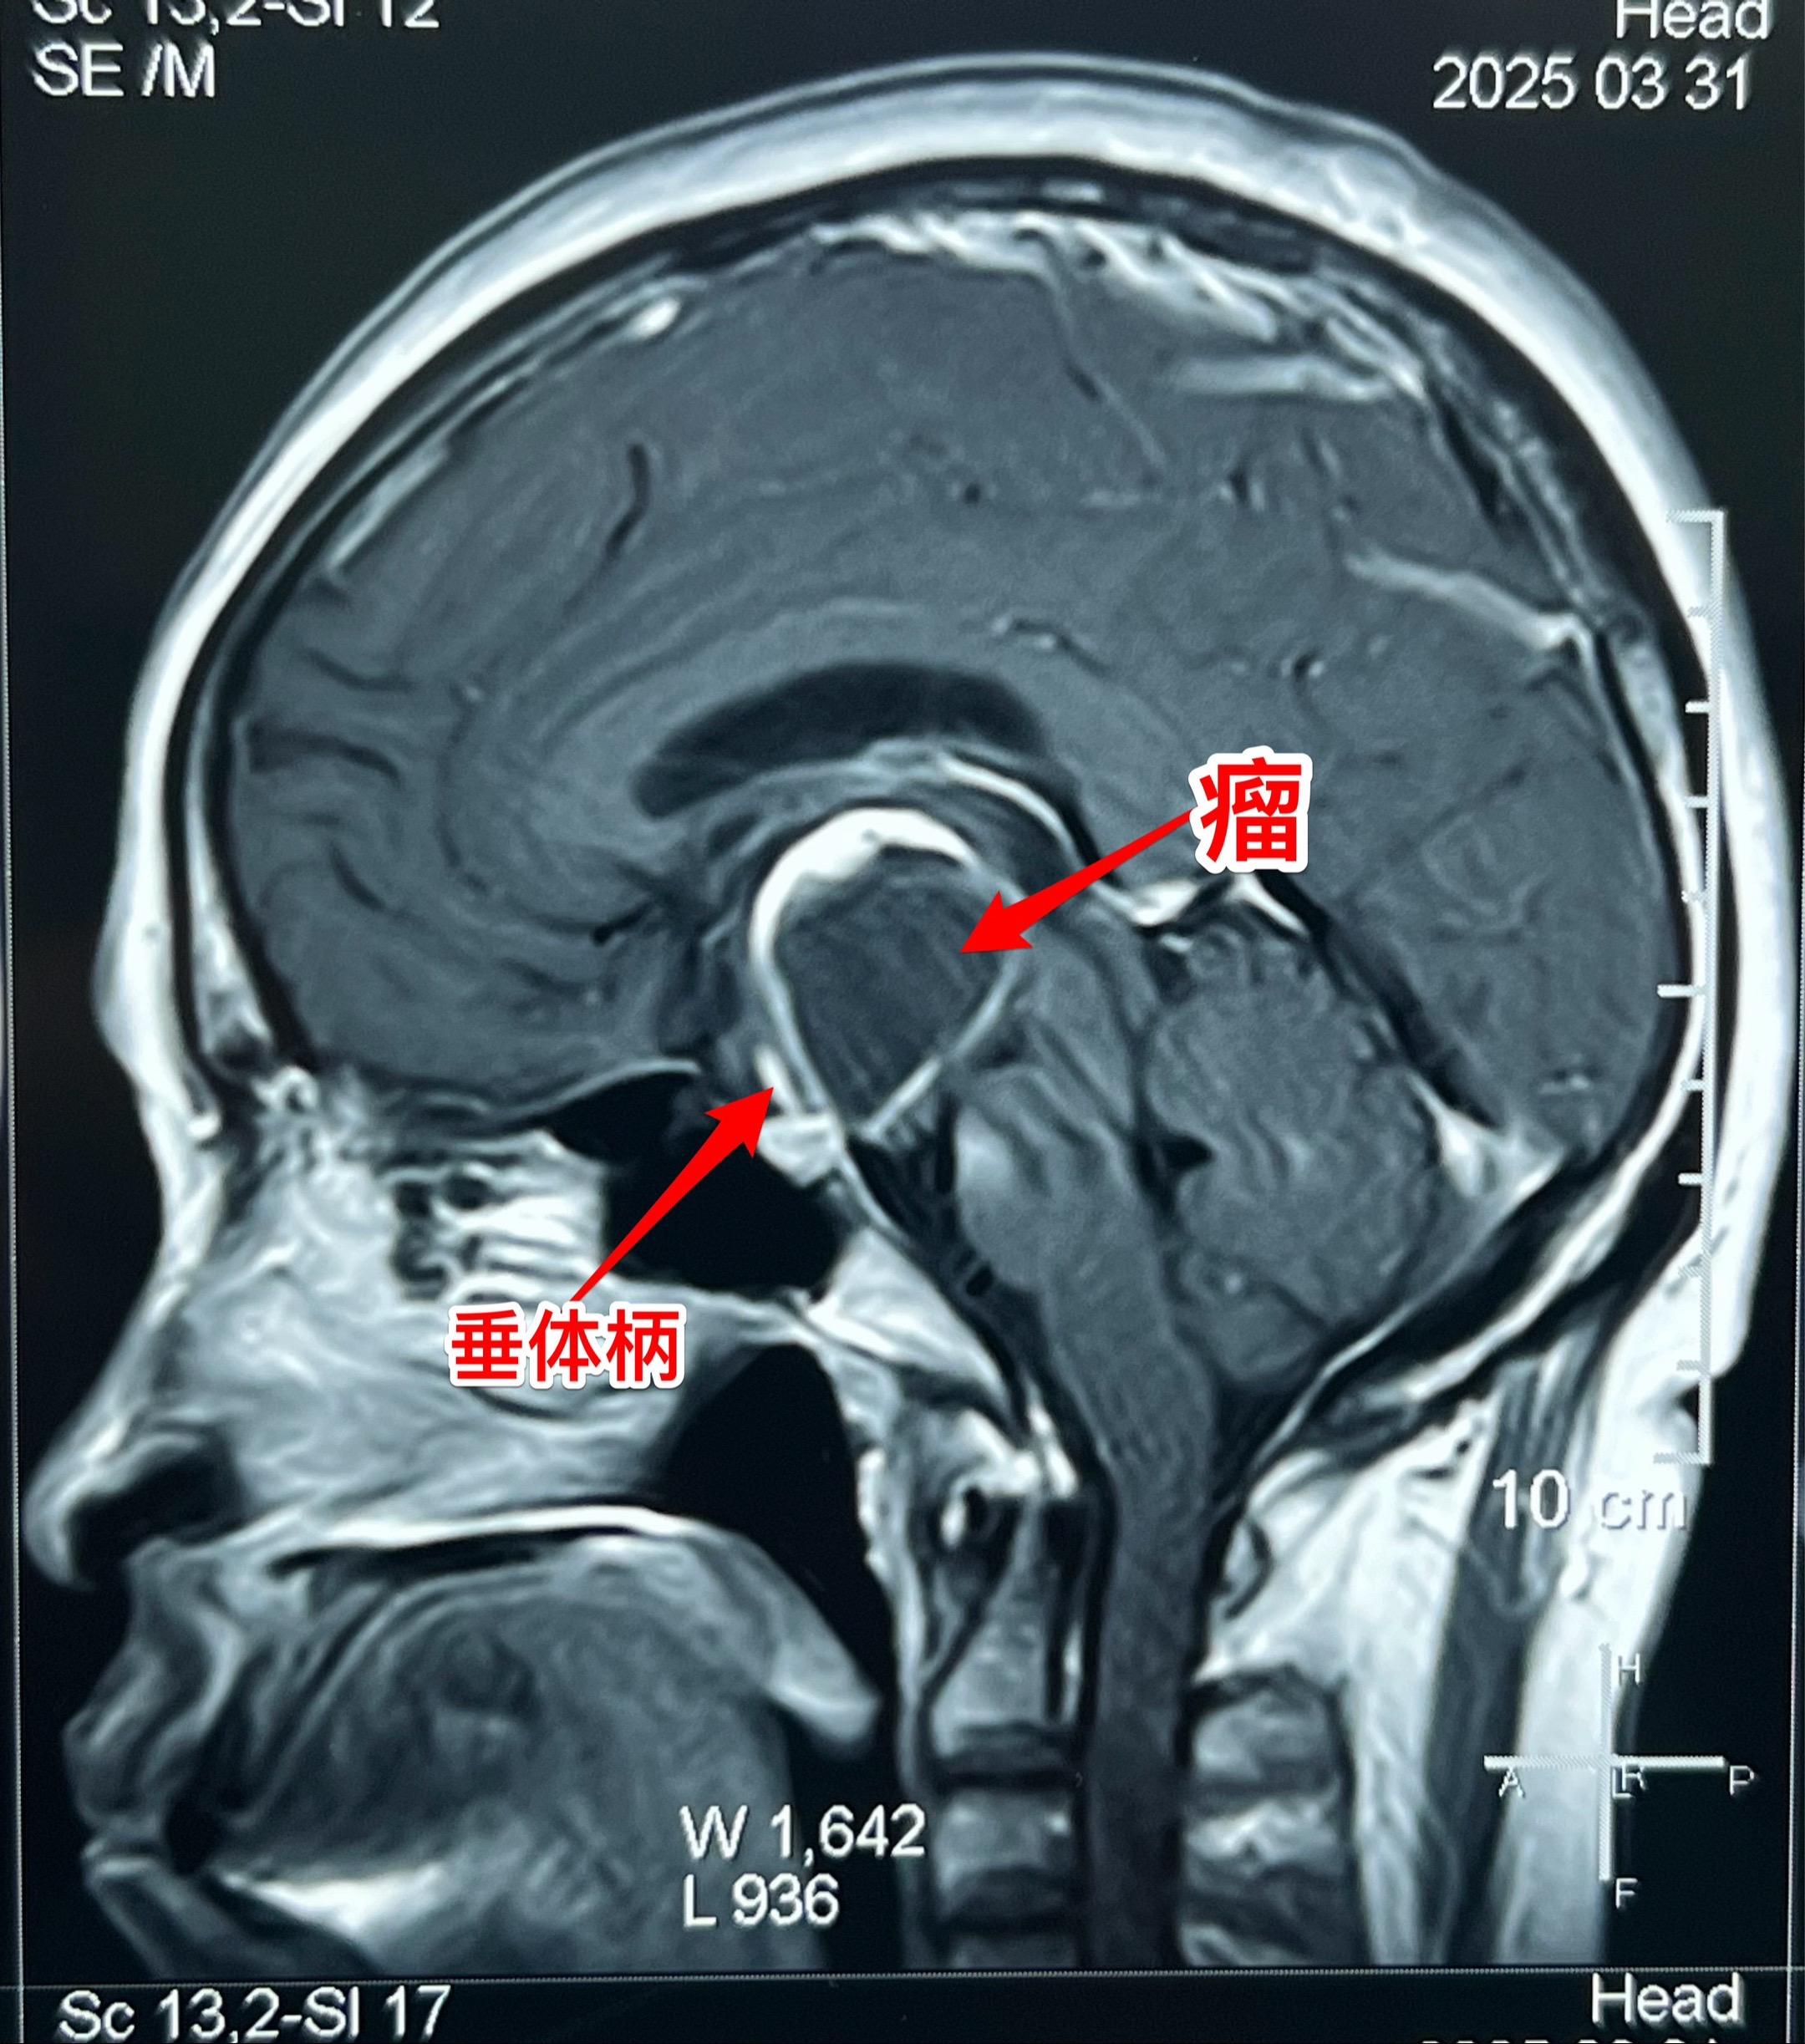

第一眼就诊断为颅咽管瘤,病理报告却不是。55岁女性因记忆力下降,有时思维糊涂就医,行脑部磁共振和CT检查发现鞍上区域囊性肿瘤,伴有钙化。 鞍上的囊性肿瘤伴有钙化,病人年龄55岁,第一印象就是颅咽管瘤。这是常规思维。 手术中发现肿瘤边界不清楚,肿瘤的钙化也不是颅咽管瘤那样的白色钙化,送了两次快速冰冻病理检查,报告提示是胶质瘤。 临床上看病首先考虑的是常见病,读书的时候老师就是这样教的。 事实上,临床上常见病能见到,罕见病也能见到。通常情况下下丘脑胶质瘤是